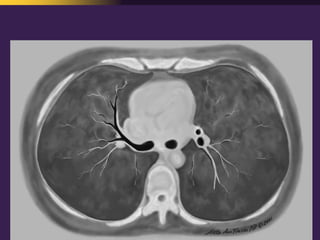

This document discusses mediastinal pathology using a compartmental approach. It describes the anatomy of the mediastinum and divides it into anterior, middle, and posterior compartments. Each compartment contains different structures and has a characteristic distribution of lesions. For example, 50% of lesions occur in the anterior compartment, which contains the thymus. The thymus is the most common site of lesions in the anterior compartment. Thymomas are the most common epithelial tumors of the thymus and mediastinum.